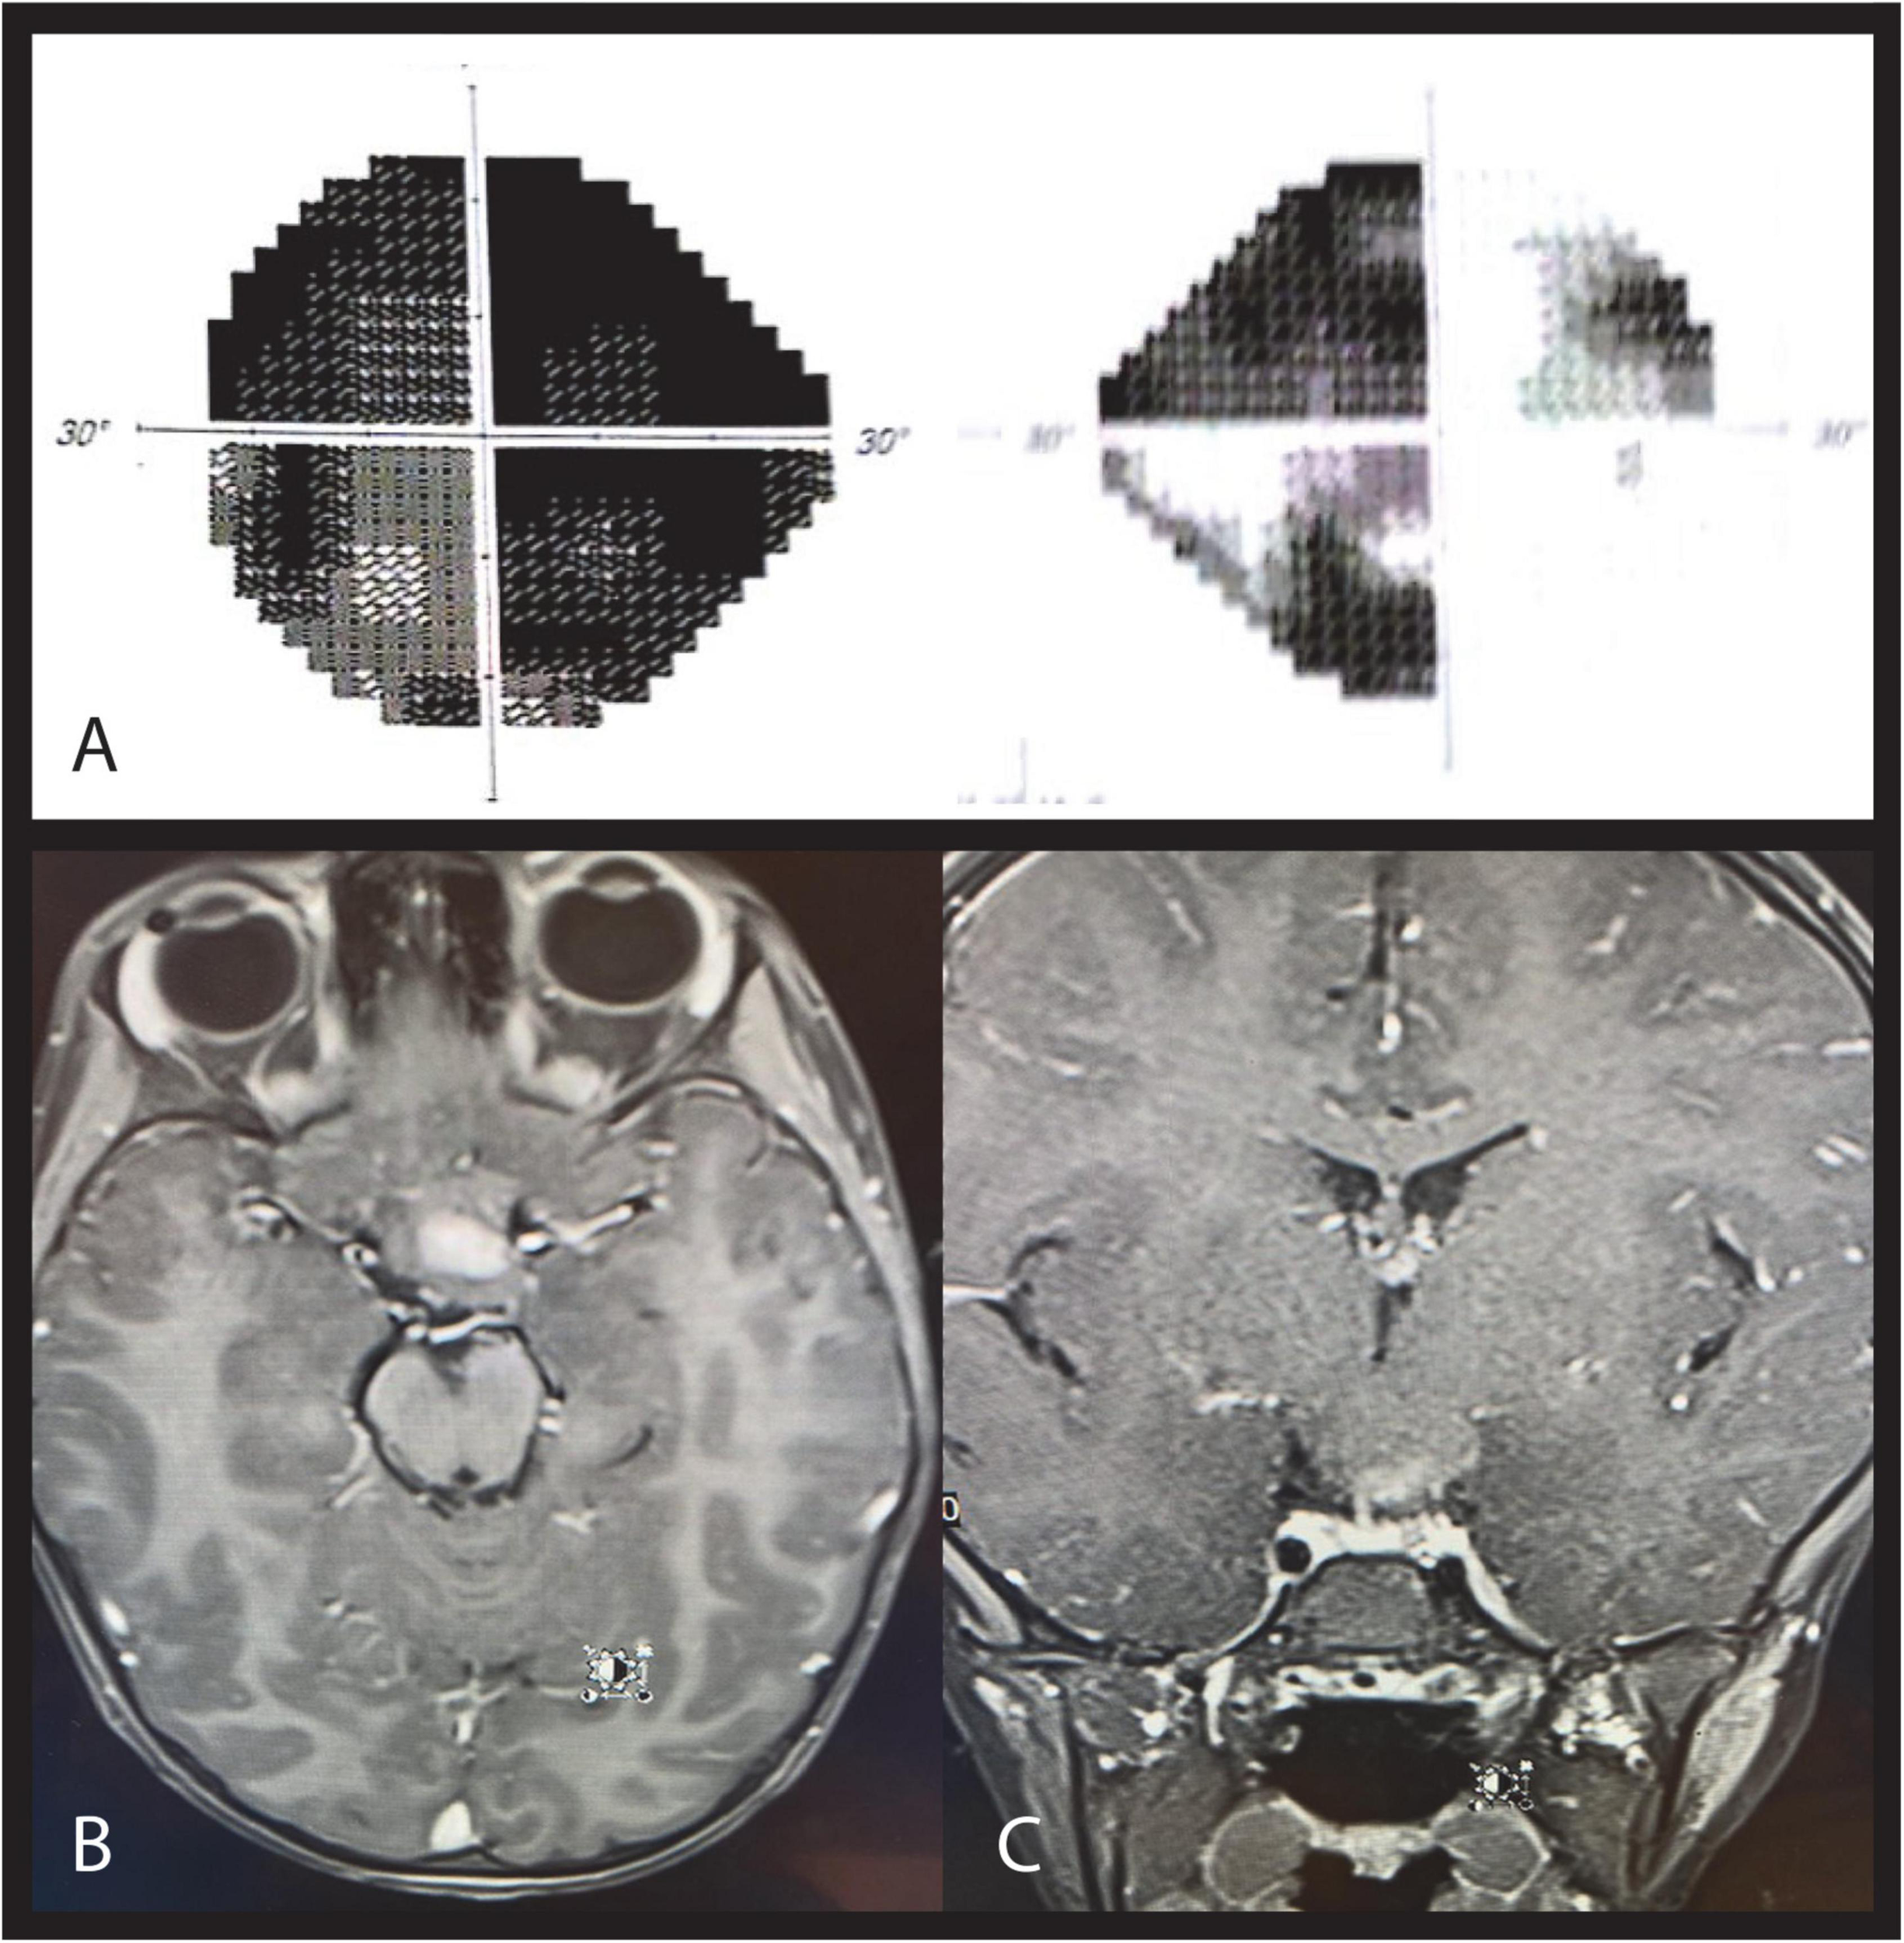

FIGURE 2

Case 2. Automated perimetry shows left homonymous hemianopia in the left (A) and right (B) eye. OCT demonstrates RNFL thinning in the left nasal and temporal (C) and right superior and inferior quadrants (D). MRI T1 coronal (E) and axial imaging. (F) After contrast show a ring enhancing lesion involving the hypothalamus and right optic tract (arrow) causing posterior compression of the chiasm consistent with low -grade glioma.